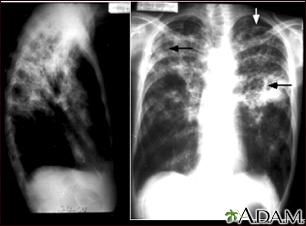

Tuberculosis, advanced - chest x-raysBackTuberculosis, advanced - chest x-raysTuberculosis is an infectious disease that causes inflammation, the formation of tubercles and other growths within tissue, and can cause tissue death. These chest x-rays show advanced pulmonary tuberculosis. There are multiple light areas (opacities) of varying size that run together (coalesce). Arrows indicate the location of cavities within these light areas. The x-ray on the left clearly shows that the opacities are located in the upper area of the lungs toward the back. The appearance is typical for chronic pulmonary tuberculosis but may also occur with chronic pulmonary histiocytosis and chronic pulmonary coccidioidomycosis. Pulmonary tuberculosis is making a comeback with new resistant strains that are difficult to treat. Pulmonary tuberculosis is the most common form of the disease, but other organs can be infected. E-mail FormEmail ResultsName:Email address:Recipients Name:Recipients address:Message: